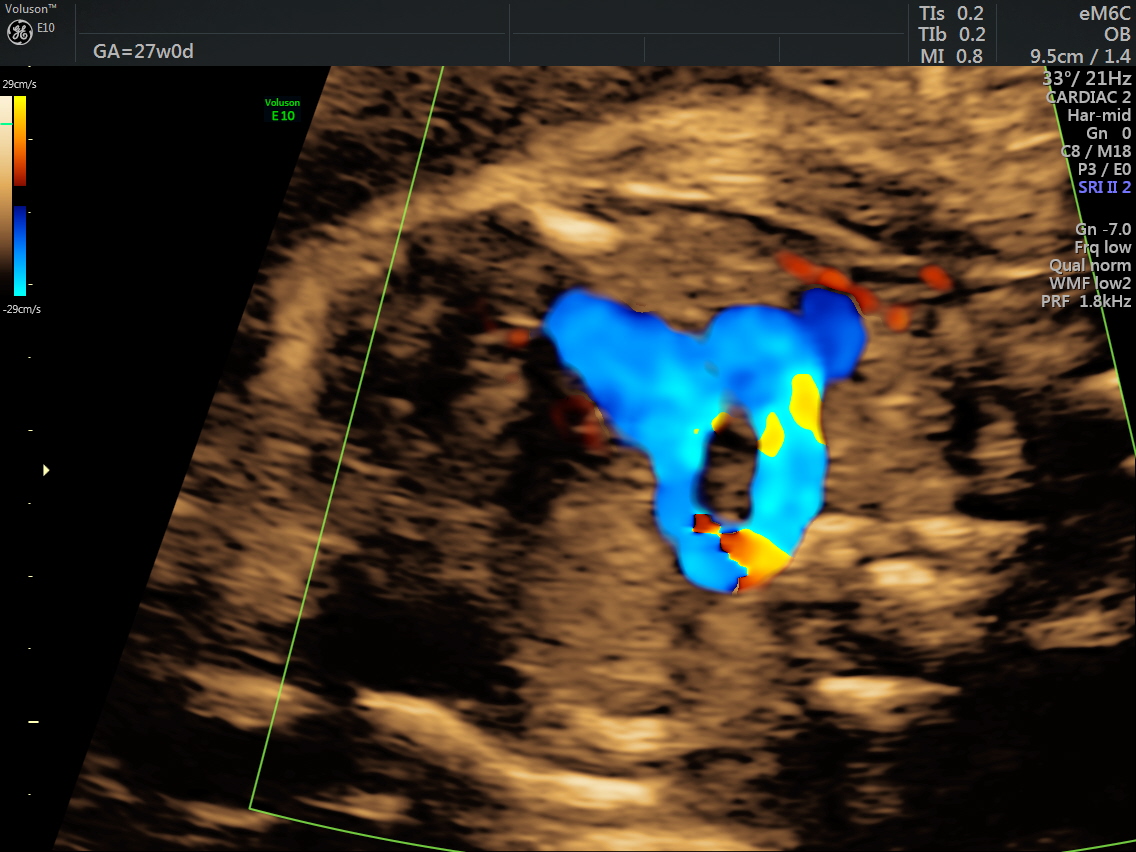

RT AORTIC ARCH_15 Published June 17, 2016 at 1136 × 852 in Rt aortic arch and aberrant left subclavian artery ← Previous Next →